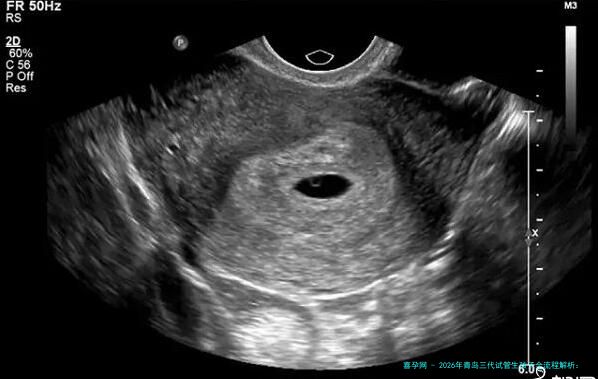

在促排期间,当卵泡成熟完成达到必须标准时,大夫会通过超声疏通下进行卵子促排手术。